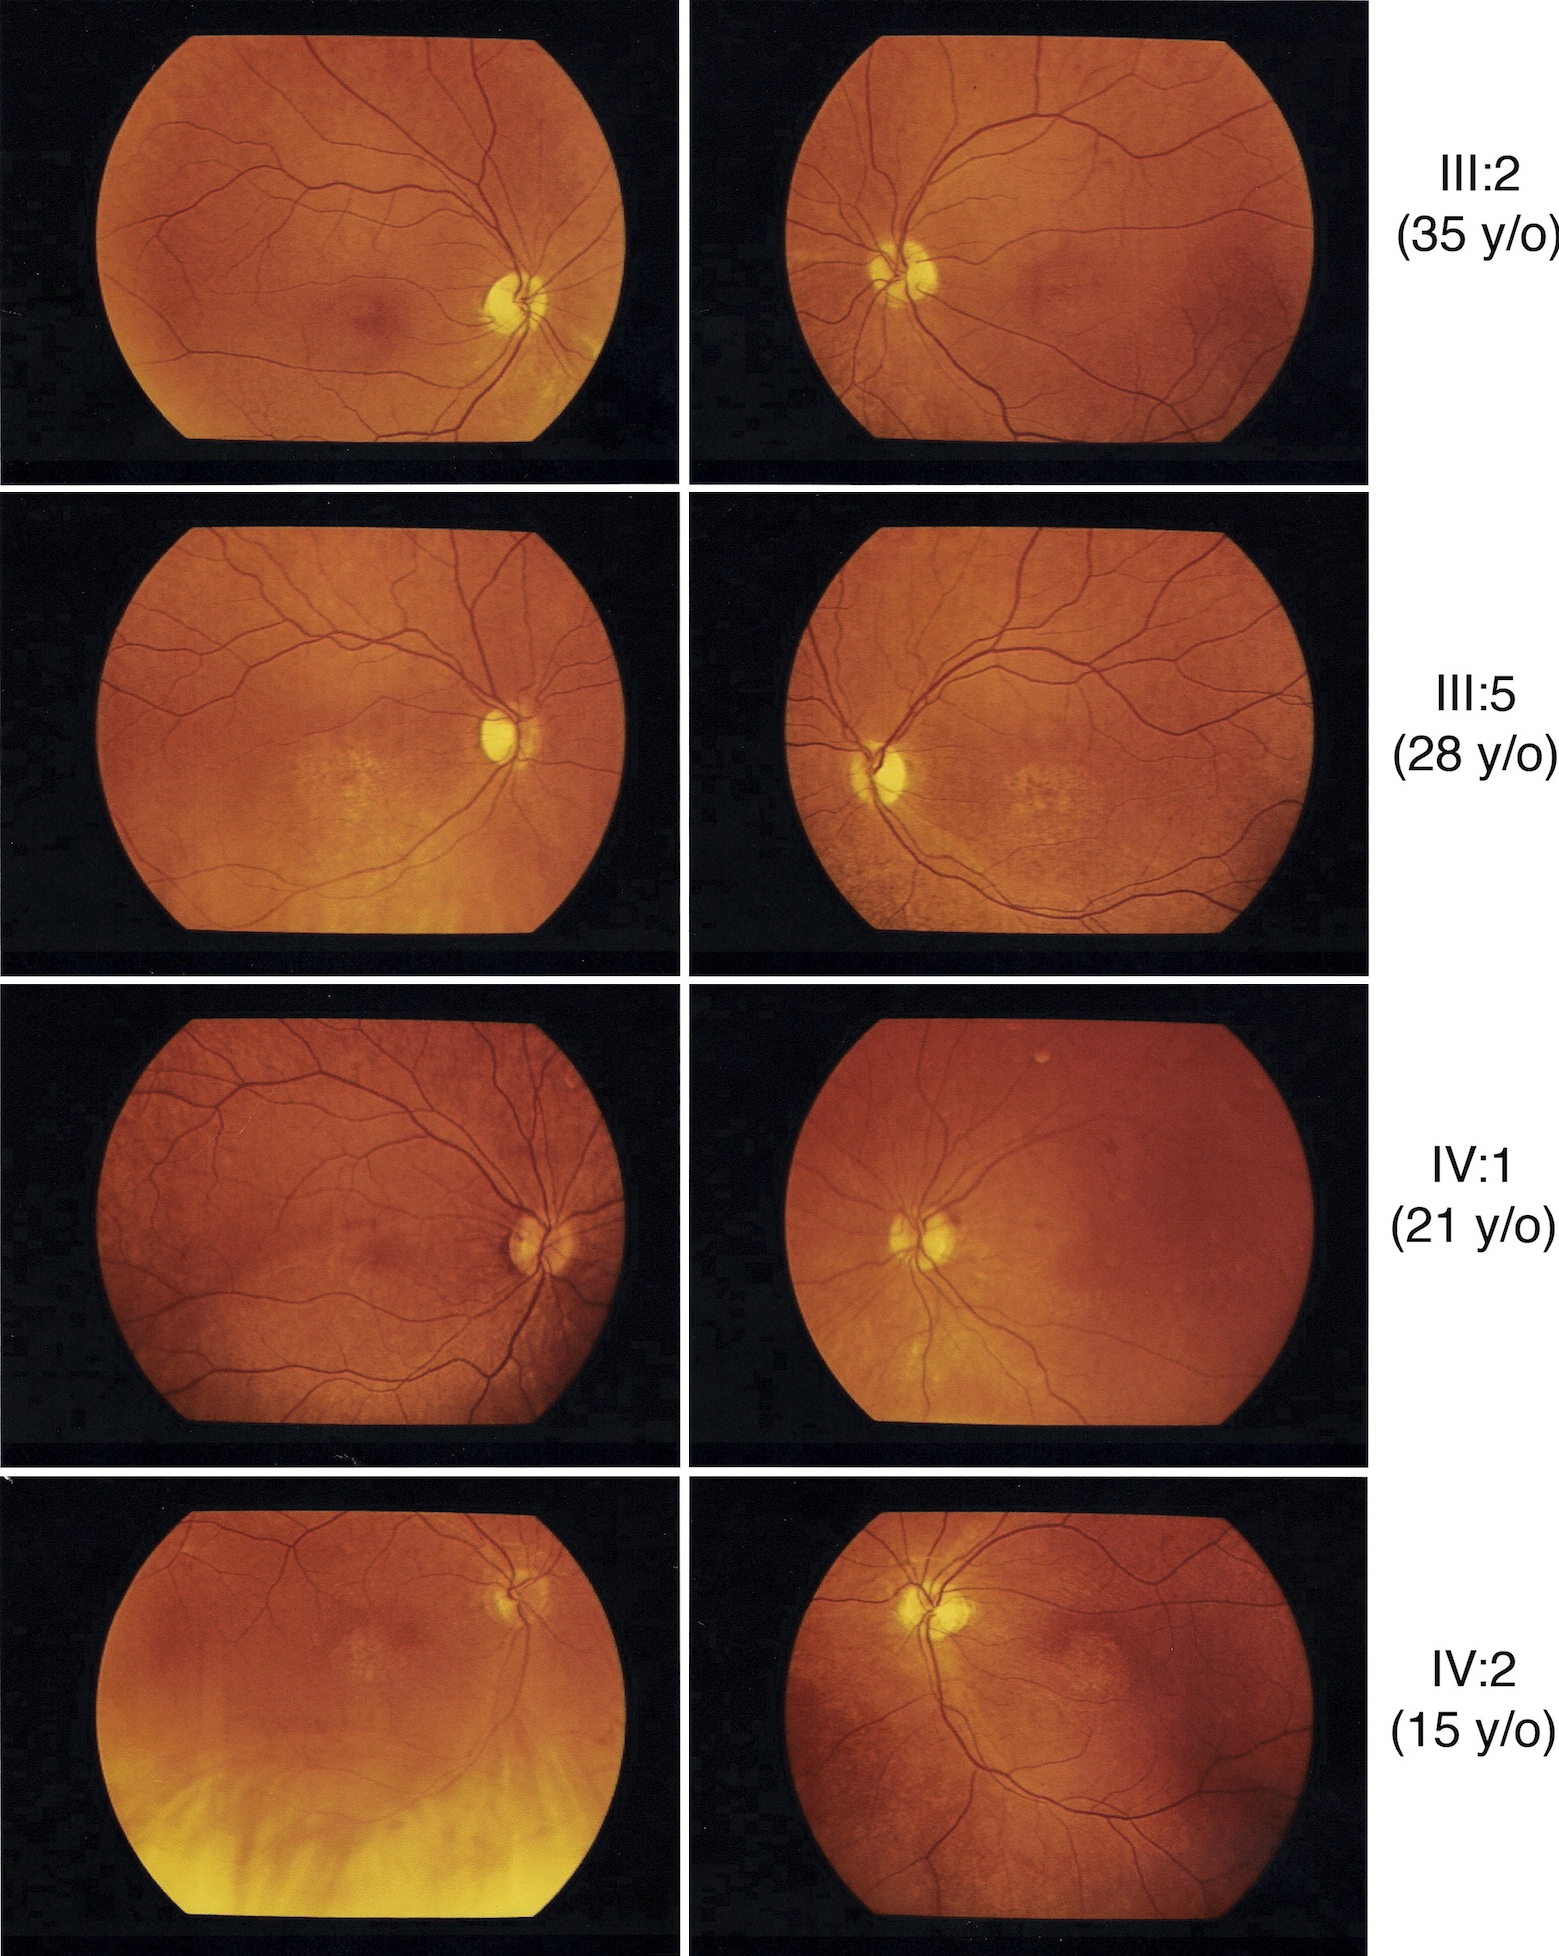

Figure 5 of Garcia-Hoyos, Mol Vis 2011; 17:1103-1109.

Figure 5. Fundus photograph of five different patients of the families with p.R838P mutation in GUCY2D. Older patients had a more severe phenotype compared to the younger generation, and to the Goldmann kinetic perimetric fields of patients III:5 and IV:2. Fundus description for these five patients has been summarized in Table 1.